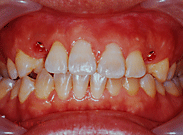

| 右下6番パーフォレーションによる骨吸収のため抜歯。両隣在歯がノンカリエスのためインプラントを選択。 |